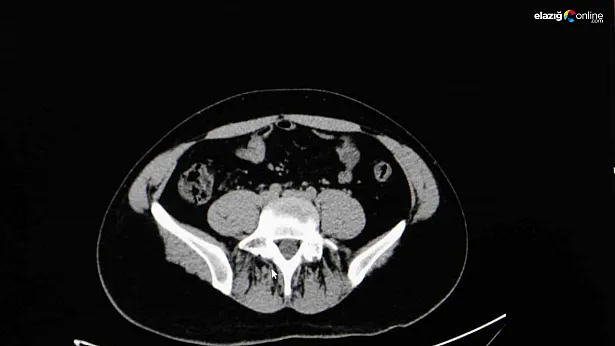

Diyarbakır Dicle Memorial Hastanesi’nde görev yapan Üroloji Uzmanı Op. Dr. Birgi Ercili “Sistit, aslında idrar torbası dediğimiz mesanenin iltihabıdır. Daha çok enfeksiyon sebepleriyle oluşur. Sistin daha çok sebebi idrar yoluna genital bölgeden ulaşan mikroorganizmalardır. Özellikle kadınlarda sistit dediğimiz durum çok fazla görülür. Çünkü kadınlarda üretra dediğimiz idrar yolu, erkeklere göre oldukça kısadır. Vajina ve anüse yakın olduğu için oradan gelen mikroorganizmaların idrar yolu aracılığıyla mesaneye ulaşması daha kolaydır. Kadınların yarısı hayatlarında muhakkak en az bir defa bu hastalığı geçirmektedir” ifadelerine yer verdi.

Sistitin sık görülen belirtilerinden idrar yanması ve az idrar yapma olduğunu ifade eden Ercili, “Sistit geliştiğinde özellikle idrarda yanma, sızı, sık sık ve az idrar yapma, damla damla idrar yapma, kasık ve alt karın bölgesinde ağrı, idrarda kan ve bulanık idrar görülebilir. Bazen de kadınlarda ilişki sonrası ağrı görülebilir. Genital hijyene çok dikkat edilmemesiyle, tuvalet temizliğini arkadan öne doğru yapılmasıyla mikropların idrar yoluna daha hızlı şekilde ulaşabildiğini görmekteyiz. Bunların dışında nemli çamaşırlarla beklemek, sık çamaşır değiştirmemek, az sıvı almak sistite sebep olabilmektedir. İlişki sonrasında da yine idrar yolunda tahriş meydana geldiği için sistit durumlarını görebilmekteyiz” diye konuştu.